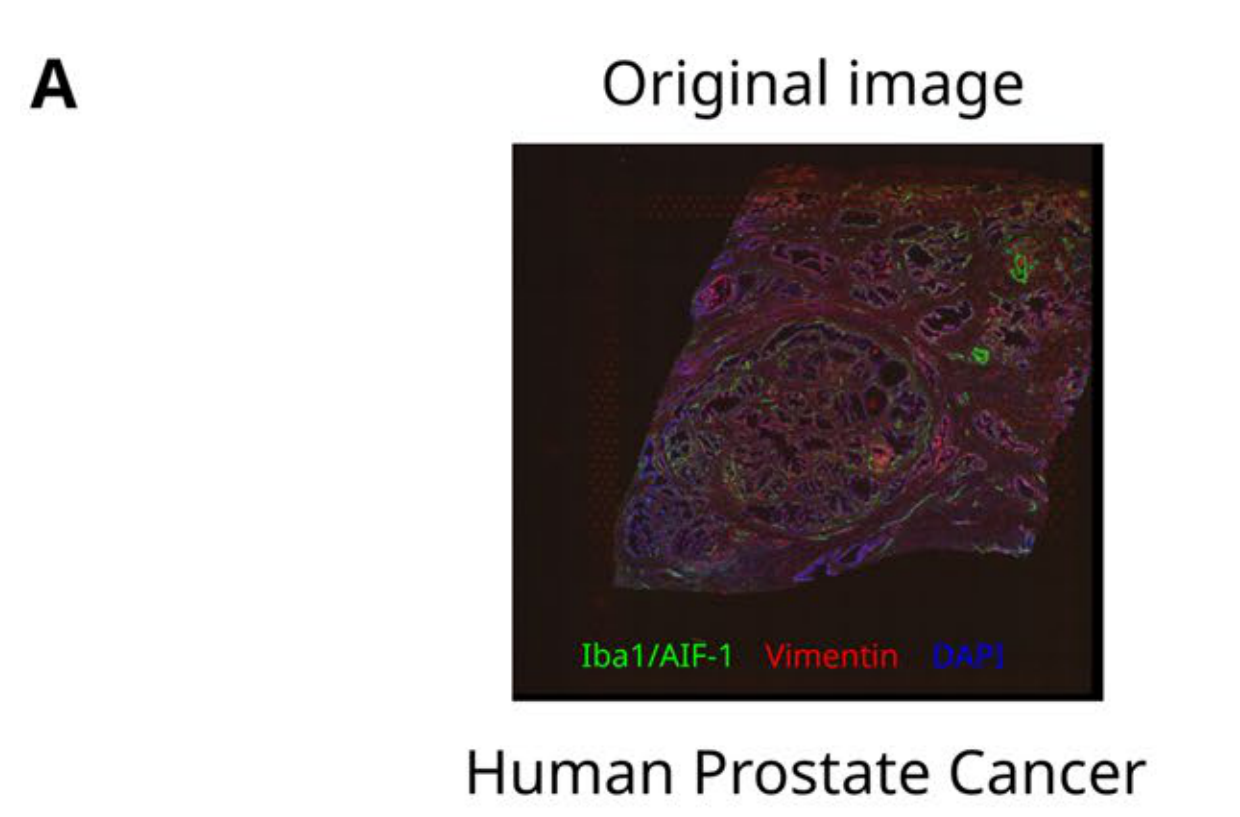

Allam et al., 2021

Spatially visualized single-cell pathology of highly multiplexed protein profiles in health and disease

Condition Dimension

Categorical

Data

Modality

Imaging-based

Resolution of observation

Cellular

Visualized Elements

ObservationRelationshipStatistic

Biological

MolecularSystemic/IntegrativeTissue

Abstraction

NonePartial

Chart Type

Dot ChartFlourescence tissue imageScatterplot

Communicative/Contextualization

AnnotationHighlighting

Comparative Design

Explicit encodingJuxtaposition

Layout

LinearSpatial : Physical

Scalability Strategy

Sampling/Filtering

What is the spatial localization and expression correlation between markers in both healthy and diseased tissues?